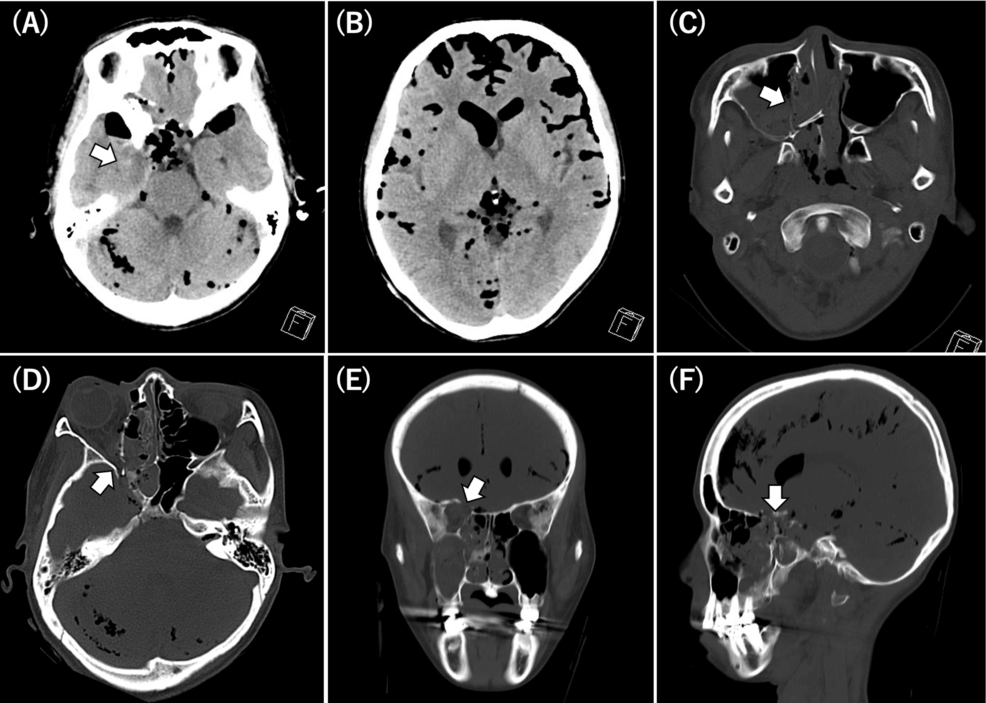

pneumocephalus, the presence of air within the cranial cavity, is a frequently observed finding in cases of head trauma. While often benign and self-limiting, extensive pneumocephalus - particularly following high-energy mechanisms like electric scooter accidents - demands immediate and meticulous neurotrauma care.This article details the clinical presentation, diagnostic approaches, and current management strategies for meaningful pneumocephalus in the context of scooter-related head injuries. Keywords: pneumocephalus, traumatic brain injury, electric scooter accident, neurotrauma, head injury, intracranial air.

Diagnostic Evaluation: Imaging Modalities

Prompt and accurate diagnosis is crucial. The following imaging modalities are essential:

Computed Tomography (CT) Scan: The primary imaging modality for evaluating pneumocephalus. CT scans readily demonstrate the presence and location of intracranial air. Non-contrast CT is preferred initially.

Magnetic Resonance Imaging (MRI): More sensitive than CT for detecting small pneumoceles and subtle dural tears. MRI is particularly useful in evaluating chronic pneumocephalus.

High-Resolution CT (HRCT) of the Sinuses: Essential for identifying sinus fractures and assessing the extent of sinus involvement.